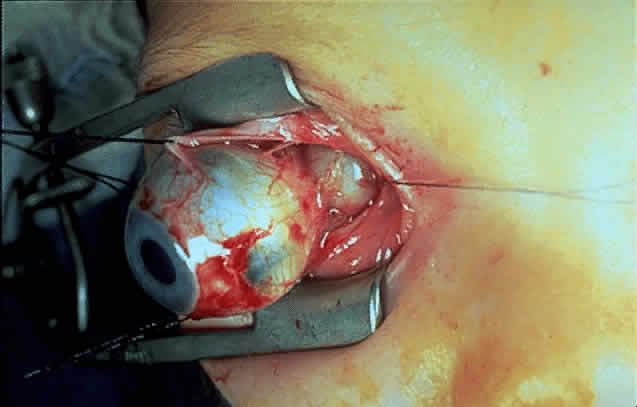

Gross examination of optic nerve gliomas usually reveals a smooth, fusiform, intradural

enlargement of the optic nerve (Fig. 6). After extending through the optic canal in a dumbbell fashion, there